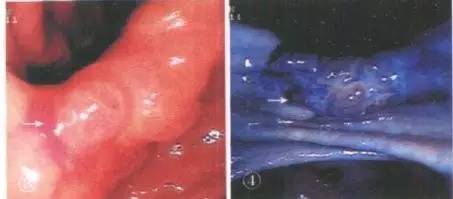

2、美蓝

美蓝染料可与癌细胞所分泌的粘液紧密结合,并可向癌组织间隙侵越。在病灶着色区呈现蓝色的深浅,与癌变细胞分泌的粘液量即恶性坏死物的多少密切相关。细胞在异型分化的过程中,分化程度越差,分泌粘液量就越多。美蓝染色随着癌细胞分泌粘液的逐渐增多,其着色的程度也逐渐加深。癌和各类异型增生的恶变程度不同,美蓝染色的程度亦各异,由此根据异型增生粘膜和早期胃癌经内镜下直接喷洒低浓度美蓝染色后,其着色区图像同组织学诊断明显相关的特征和规律,在已取组织证实为早期胃癌及癌前病变区进行,(前通过向胃膜喷洒药物观察粘膜颜色改变可清晰地显示出病变的隆起高度、凹陷深度、底部及皱襞的形态等,从而较准确地判定癌的浸润深度,从而初步确定病变的范围、大小、高度,使普通内镜检查治疗时容易遗漏的一些微小病变通过染色得以发现。

胃角部美蓝染色,癌变区域染色深蓝